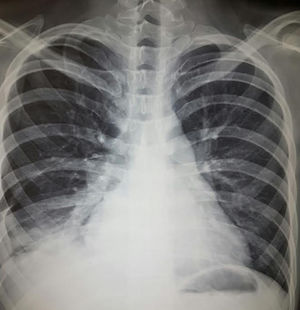

Diagnóstico. Puede corroborarse ante los hallazgos clínicos, el descenso no explicable de hemoglobina, hallazgos radiográficos característicos y la respuesta favorable al tratamiento. En la figura 4 se muestra radiografía con imágenes alveolares características de hemorragia alveolar. Algunas herramientas que pueden contribuir al diagnóstico son:

Mujer de 20 años con historia de lupus eritematoso sistémico de 4 años de evolución. Con vasculitis necrosante en miembros inferiores, psicosis, eritema, fotosensibilidad, trombocitopenia, linfopenia, anemia grave, VDRL+ y AAN 1:640 homogéneo y periférico. Últimos meses con disnea progresiva hasta la de mínimos; últimos días con incremento de tos, disnea y hemoptisis; hemoglobina 3g, hipoxemia, proteinuria nefrótica y sedimento telescopiado. Tele de tórax muestra imágenes alveolares compatibles con hemorragia alveolar difusa. Recibió metilprednisolona 1g 3 días y ciclofosfamida con adecuada respuesta.